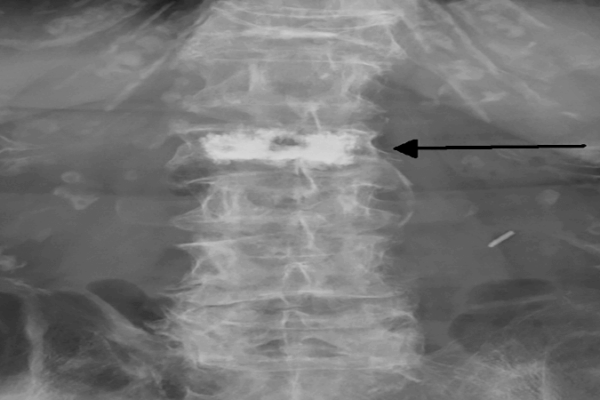

Rizotomia ou Denervação Facetária

O que é Rizotomia? A Rizotomia, ou também chamada de denervação facetária, é um procedimento minimamente invasivo percutâneo para alívio da dor causada por degeneração das articulações facetárias que estão localizadas na parte posterior da coluna. São os discos e as articulações facetárias que dão estabilidade à coluna. As articulações facetárias são responsáveis pela estabilidade […]